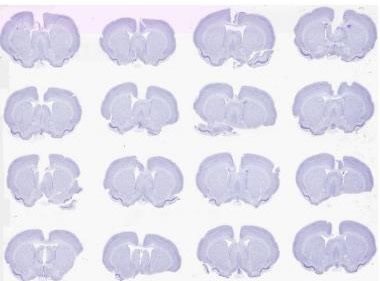

- A proprietary laser-scan lens and optical configuration enables a broad (5 to 10mm) field-of-view and therefore the imaging of more rodent brain sections per unit area (up to 48 square inches area).

Figure 2. Brightfield scan of 16 Nissil stained rodent brains on a 2” x 3” slide at 0.5 μm. Image credit: Huron Digital Pathology.